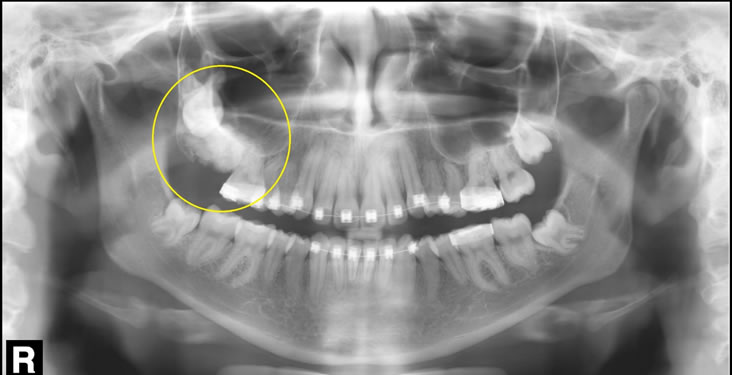

Одонтома нижней челюсти: фотографии и медицинская информация